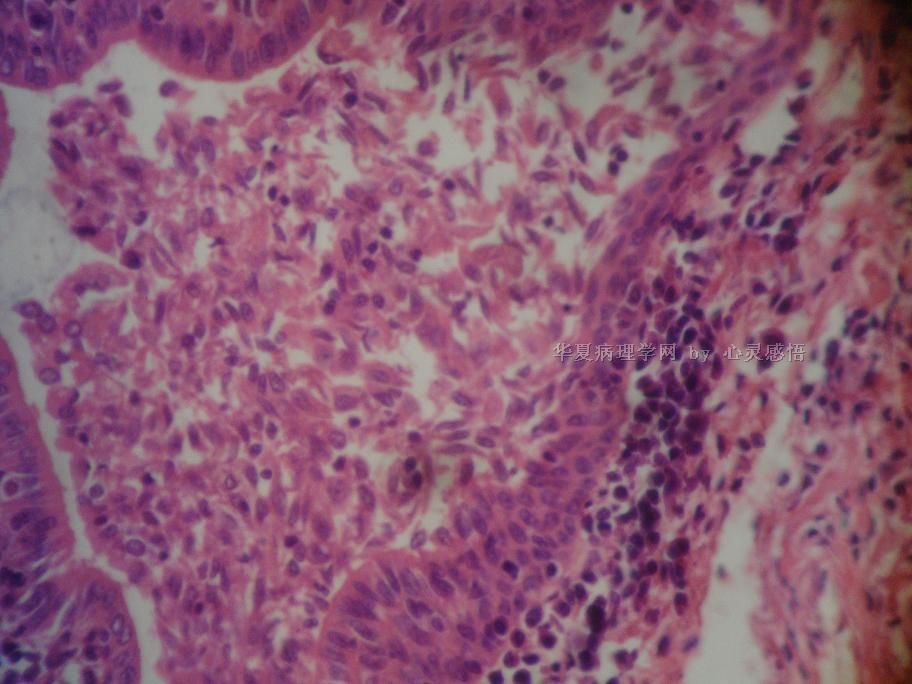

• 食道癌,淋巴结有没有转移,谢谢。图1

图1

1-6图是鳞癌。7-22图片无癌。